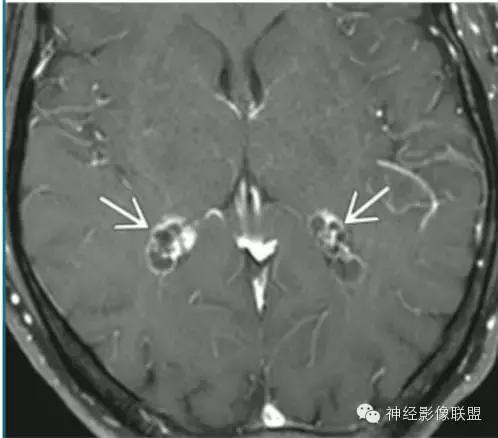

脉络丛囊肿